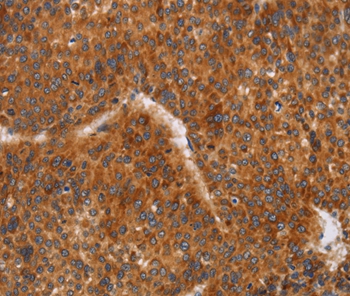

Immunohistochemical analysis of paraffin-embedded Human liver cancer tissue using #37474 at dilution 1/60.

Immunohistochemistry: 1:50-1:200